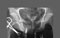

Male urethrogram Obstructed ureter 5. Examine the external genitalia in the male. (Play movie; View images: N 351, 377, 382, 387A, 387B, 390, 398, TG 6-02, 6-25A, 6-25B, 6-31)

3. Remove the peritoneal covering of the bladder and examine. (Play movie; View images: N 360, 361, 362, 366, 402, 403, 406, 407, 408, 410, TG 6-07A, 6-07B, 6-08A, 6-08B, 6-10A, 6-10B, 6-17A, 6-17B, 6-19A, 6-19B, 6-33, 6-34)